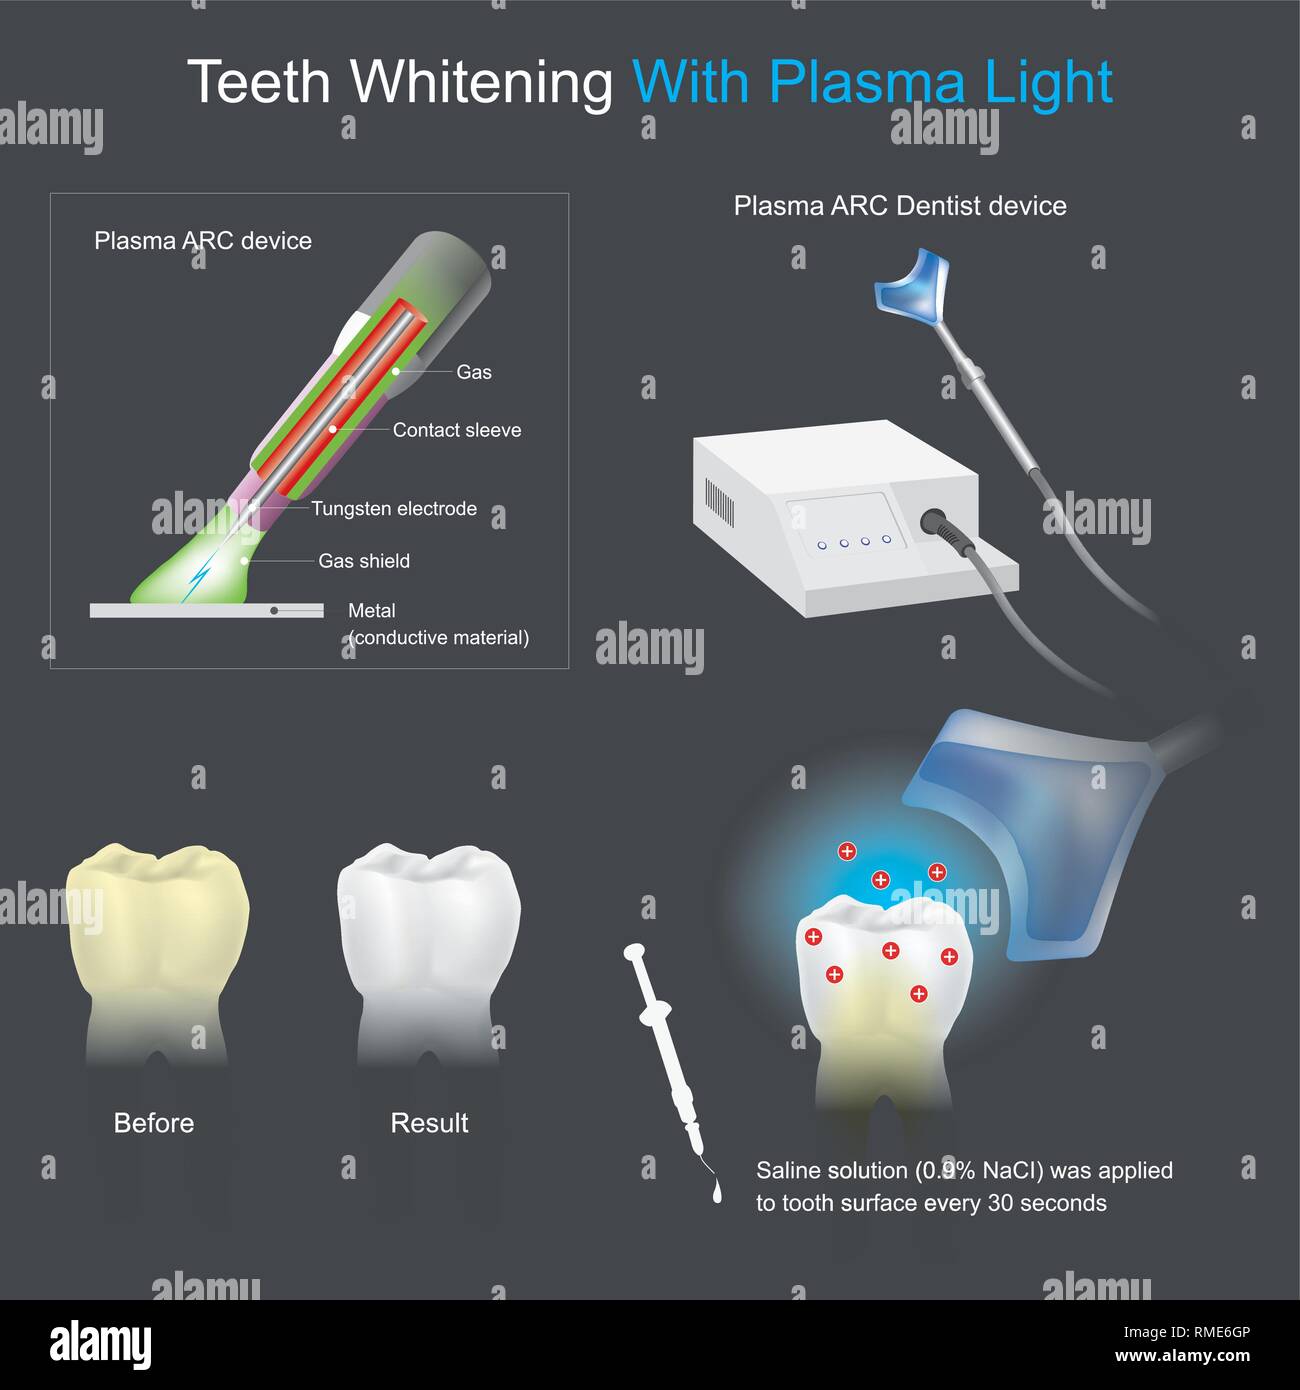

Fa sì che le macchie di colore sulla superficie del dente a scomparire per via chimica ed i metodi elettrici Illustrazione Vettorialehttps://www.alamy.it/image-license-details/?v=1https://www.alamy.it/fa-si-che-le-macchie-di-colore-sulla-superficie-del-dente-a-scomparire-per-via-chimica-ed-i-metodi-elettrici-image236340406.html

Fa sì che le macchie di colore sulla superficie del dente a scomparire per via chimica ed i metodi elettrici Illustrazione Vettorialehttps://www.alamy.it/image-license-details/?v=1https://www.alamy.it/fa-si-che-le-macchie-di-colore-sulla-superficie-del-dente-a-scomparire-per-via-chimica-ed-i-metodi-elettrici-image236340406.htmlRFRME6GP–Fa sì che le macchie di colore sulla superficie del dente a scomparire per via chimica ed i metodi elettrici